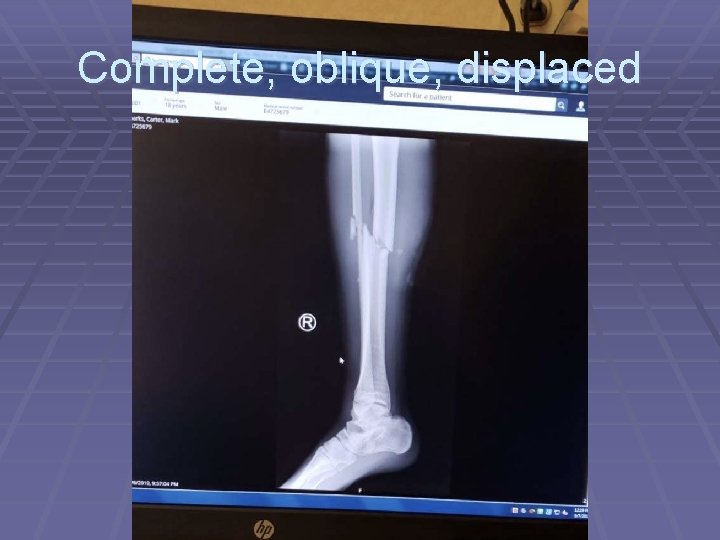

Complete, oblique, displaced